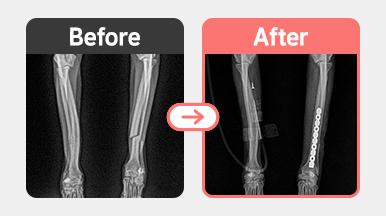

[경골 골절 수술] 러시안블루 / 2살 / 좌측 tibia 복합골절 / 이중 plate 고정

2025-11-06